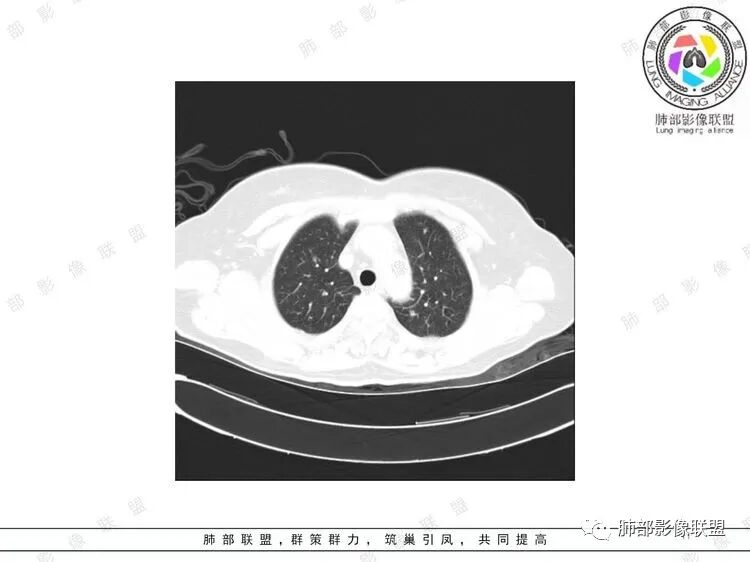

胸CT:双中下肺支气管壁明显增厚,双下肺胸膜下可见实变区。部分病变呈楔形影。

影像上:多发结节沿血管分布;双下叶支气管血管束简直增厚,偏血管,支气管通畅

首先肺部气道来源的病变不符合

因为支气管壁增厚,远端应该小气道病变,这个不是,反而是血管增粗明显

加上结节的分布,支持血管相关病变